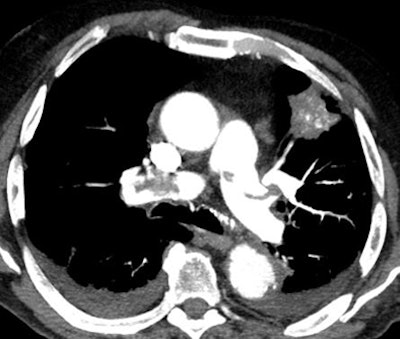

| Axial image shows extensive filling defects in the pulmonary trunk and the main pulmonary arteries. A solid lesion is seen in the left lung. Bilateral pleural effusion is also present. All images courtesy of Dr. Giulia Zamboni. |

PE was categorized as massive (affecting the main trunk) or nonmassive (segmental or subsegmental emboli), and the study team logged the prevalence of other chest findings such as pulmonary consolidation, pleural effusion and atelectasis, and tumors, primary or secondary. A venous scan of the abdomen and pelvis was added to look for DVT, and correlation between D-dimer levels and PE was calculated.

The results showed PE in 73 (30.5%) of 239 patients; of these cases, 45 (61.6%) were categorized as massive and 28 (38.4%) as nonmassive.

Collateral findings in patients with PE included pleural effusion (n = 27), parenchymal consolidation (n = 15), and tumors (n = 7). In 165 scans that were negative for PE, 75 patients had no significant findings at CT and 90 had pleural effusion (n = 66), parenchymal consolidation (n = 36), or tumors (n = 10).